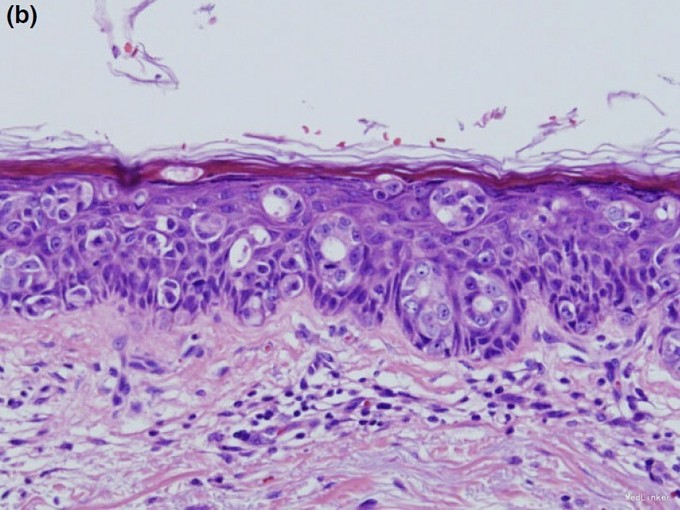

查体:枕部红斑,边界欠清,部分脱色性鳞屑性斑片中见轻度脱发(图 1)。余部位皮肤及浅表淋巴结未见异常。既往史及家族史无特殊。 辅查:皮损中部活检后组织病理:表皮内大量散在或成巢的大细胞,细胞质透明,核非典型。这些非典型细胞部分浸润于附件,而无真皮受累(图 2a)。部分细胞成管状细胞巢,部分管状结构内层细胞可见断头分泌至管腔(图 2b)。 非典型细胞免疫组化:过碘酸 - 希夫染色、阿辛蓝染色、癌胚抗原、雌激素受体、雄激素受体、细胞角蛋白 -7、细胞角蛋白 -20、囊泡病液体蛋白 -15 阳性(图 3a-e),AE 1/3 阳性;p63、黄体酮受体、S-100 蛋白及 HMB-45 阴性。腹部超声、CT、胸片及 PET-CT 等检查未见其他异常。